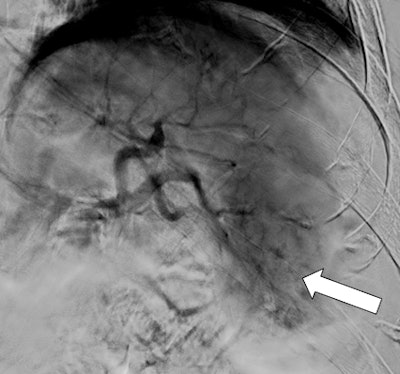

Figure 2: Axial view of CT of the abdomen demonstrates unremarkable appearance of the pancreas on arrival (white arrow).Splenic arteriogram demonstrated parenchymal injury and active extravasation, which corresponded with the CT, with identifiable contrast extravasation (figure 3A). In a location distal to the dorsal pancreatic artery, SAE was performed utilizing 0.035- and 0.018-inch coils.

Figures 3A and 3B: Splenic arteriogram demonstrates diffuse injury at the inferior pole of the spleen (above with extravasation). Coils were deployed distally to the dorsal pancreatic artery (black arrow). Postembolization arteriogram shows stasis of blood flow in the mid and distal splenic artery (below).More than 35 coils were used to reach stasis because the splenic artery was hypertrophic with a very robust flow. Postembolization control arteriogram was performed and confirmed stasis of flow within the mid and distal splenic artery (figure 3B). The patient's hemoglobin stabilized; he clinically improved and was subsequently discharged.